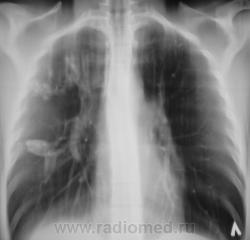

остаточные изменения перенесеннго тбц?

хотелось бы посмотреть что было раньше....

Не. не посмотрим. Что было раньше - все на пленке, а пленки в облтубе.